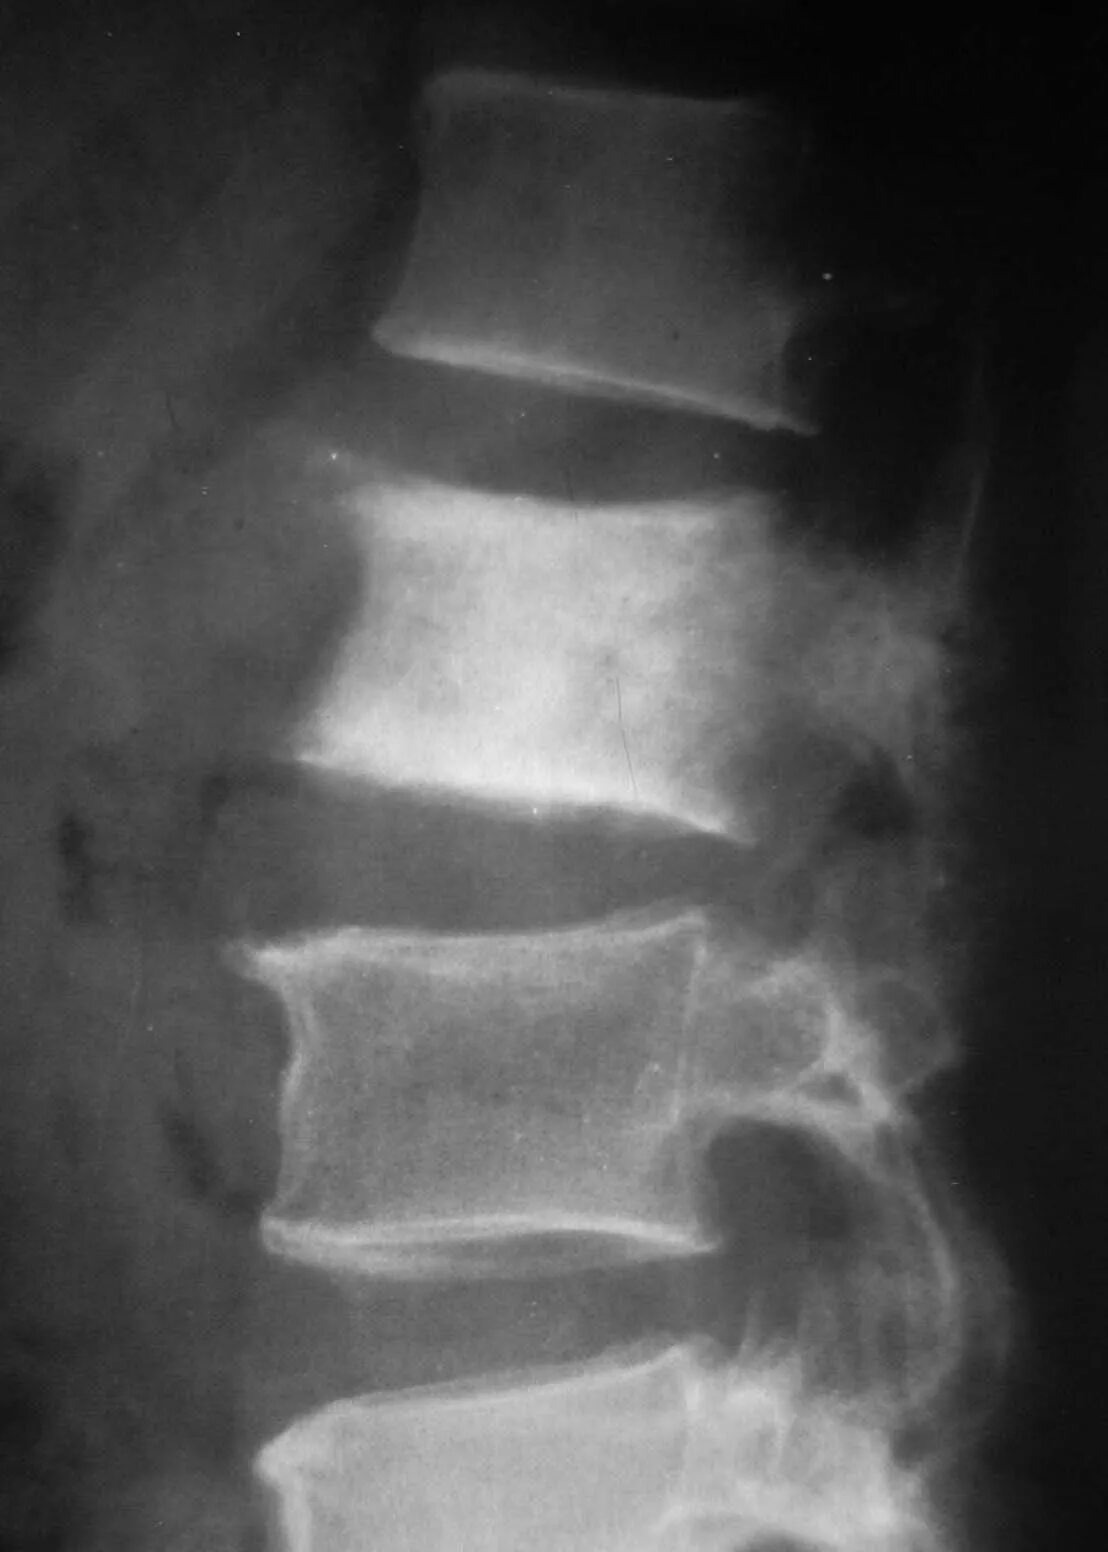

Метастазы в поясничном отделе симптомы